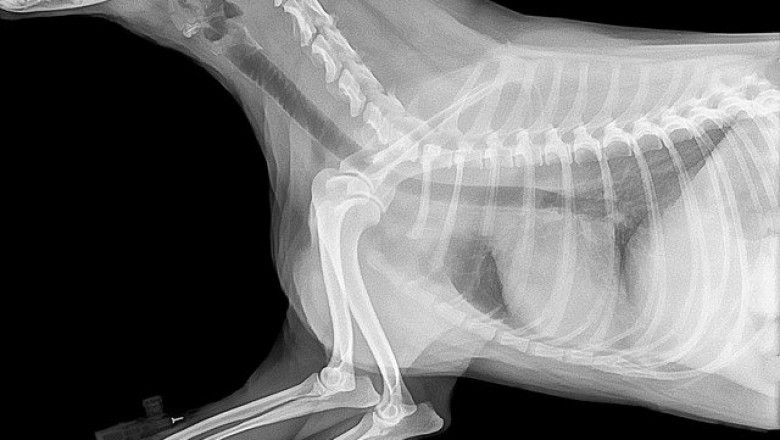

The global veterinary imaging market has been evaluated as steadily growing market and it is expected that the market will continue to grow similarly in the near future. Veterinary deals with diagnosis and treatment of diseases in animals. Veterinary imaging devices are useful in diagnosis and treatment of diseases in animals. These devices also gives clear understanding of disease or injury that helps veterinarian for treatment of animal. Increasing awareness about animal healthcare and improvement of animal life are key factors for the growth of the market. Disease pattern in animals are continuously changing and becoming more challenging for veterinarians to diagnose these diseases.

Veterinary imaging devices gives them in accurate diagnosis and further treatment. Increasing pet adoption is another major factor for the growth of the market. Increasing number of veterinarians, veterinary clinics and growing veterinary healthcare infrastructure are driving the growth for the market. Cattle are very important part of farming that have economic importance because they provides many products like milk, meat and leather. Farmers are becoming more aware about the health of their cattle which is good sign for the growth of the market. About 75% of veterinarians are working in private hospitals or pet clinics and these hospitals or clinics are spending money in advancement of technology to provide better facilities. Veterinary imaging devices manufacturers are spending money to develop innovative and usable product for the market. However there are some factors are inhibiting the growth of the market such as high cost of devices that small clinics cannot afford, lack of knowledge about new technology or products, availability of products, access to veterinary healthcare facilities, lack of skilled veterinary professionals etc.